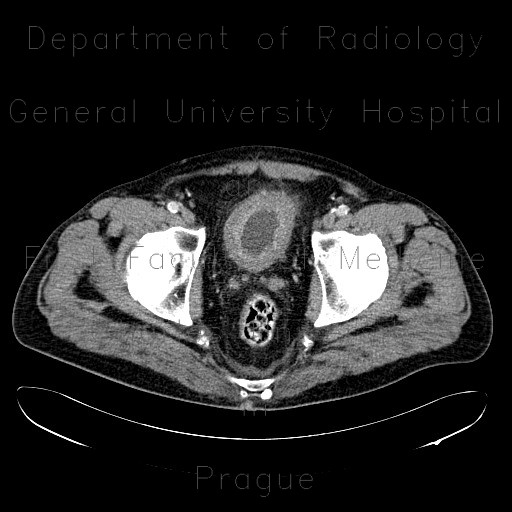

CT shows marked thickening of bladder wall with enhancing inner layer and stranding of surrounding fat.

Radiology image - Cystitis, acute cystitis, bladder: Abdomen, Urinary tract: CT - Computed tomography